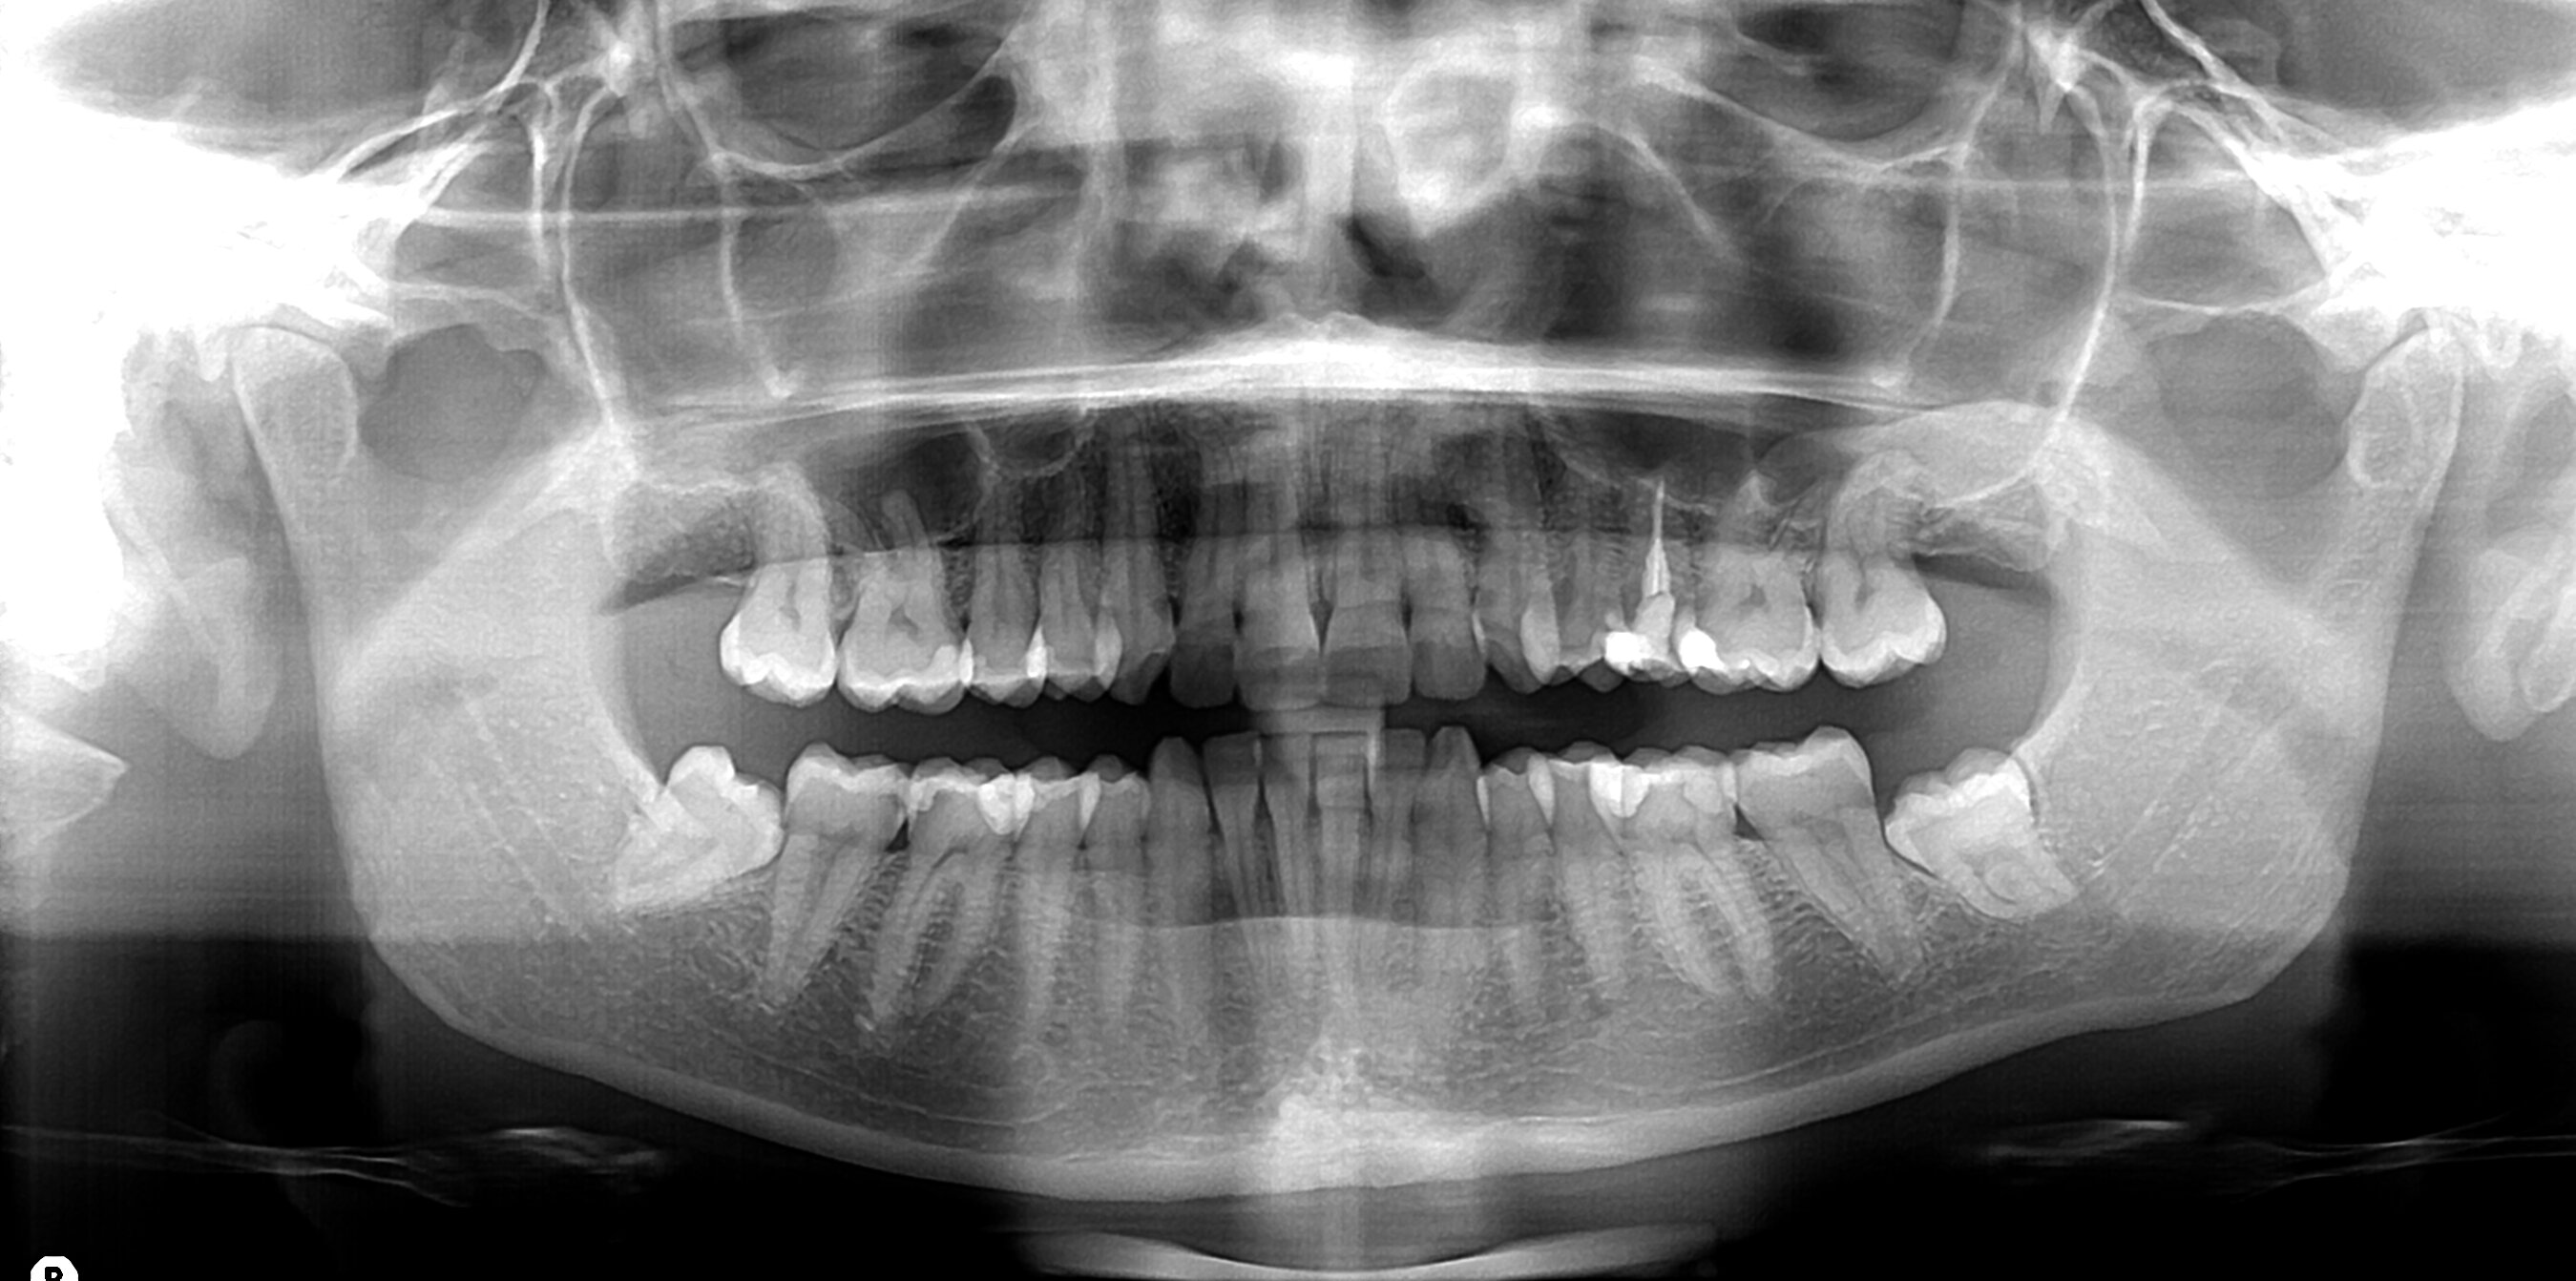

Per avere una visione completa dello stato di salute orale del paziente, e poter formulare una corretta diagnosi, il dentista integra i dati raccolti durante la visita con degli esami diagnostici, quali le radiografie dentali. Le radiografie dentali, si dividono in due macrocategorie, endorali (lastrine) ed extraorali (panoramica o ortopantomografia), restituiscono l’immagine dei denti e dei tessuti ossei mascellari che li sostengono, permettendo l’individuazione di: Attraverso le RX endorali si analizzano i denti e le strutture di supporto, inserendo nel cavo orale delle piccole pellicole. Le RX extraorali, invece, permettono una visione completa delle due arcate, delle ossa della bocca, del cranio e del profilo del viso, molto utili in fase di prima visita. La diagnosi radiografica consente al dentista di individuare precocemente problematiche dello stato di salute dei tessuti molli e di quelli duri della bocca del paziente. In ortodonzia e pedodonzia l’utilizzo delle radiografie è finalizzato, ad esempio, a tenere sotto controllo il processo di crescita dei denti e delle ossa mascellari, per intervenire tempestivamente in caso di problemi dello sviluppo. La pericolosità delle radiografie è legata strettamente alla quantità di radiazioni ionizzanti per tempo di esposizione. Ad esempio, per ottenere le radiografie dei denti posteriori, composte da 2 o 4 immagini, il paziente è esposto a circa 0.005 millisievert (mSv) di radiazioni. Nel nostro studio, inoltre, utilizziamo apparecchiature radiografiche digitali di ultima generazione, che hanno ulteriormente ridotto le dosi di radiazioni necessarie (fino al 90% in meno), assicurando comunque alti standard qualitativi dell’immagine. Anche le donne nella fase della gravidanza possono sottoporsi senza rischi particolari alle radiografie dentali, in quanto è la sola zona interessata dal posizionamento del radiografico ad essere direttamente investita dai raggi, Naturalmente è sempre importante avvisare il dentista del proprio stato, o anche solo del sospetto di poter essere in stato interessante. L’uso del grembiule mette il bambinoa al riparo dalle radiazioni, praticamente annullando qualsiasi rischio. Per avere un’idea, le dosi di radiazioni che si ricevono durante un volo aereo di piccolo o medio raggio sono 2 volte superiori a quella di una panoramica dentale e 10 volte superiori rispetto ad una radiografia endorale. Questo accade per esposizione alle radiazioni del sole, le quali in alta quota sono meno filtrate dalla atmosfera. Potrete però notare che durante l’esecuzione di una radiografia, noi usciremo dalla stanza, questo perché altrimenti, saremmo esposti alle radiazioni molte volte al giorno e per un periodo lungo di tempo legato alla nostra professione. Le radiografie dentali, quindi, ci sono utili per rivelare la presenza di problemi che ad occhio nudo non sempre possono essere diagnosticati (soprattutto le lesioni allo stato iniziale). Per noi dello Studio Dentistico Orioli è fondamentale la prevenzione, importante per curare in tempo possibili lesioni ed evitare che diventino, se non trattate, irreparabili. Il nostro obiettivo è evitarti fastidiosi dolori e mal di denti improvvisi! Per ulteriori informazioni o una prima visita di controllo, non esitare a chiamarci. Siamo pronti a prenderci cura del tuo sorriso!!